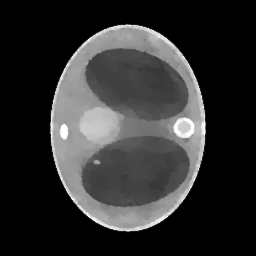

We assume to measure a total of photons and compute synthetic data from eq. 11 for a phantom electron density modeling a transversal slice of a human thorax. The phantom (see fig. 2(b)) consists of characteristic functions of ellipses of different sizes and opacities and is a modified version of an earlier phantom which was used in [12]. It is 28.4 cm resp. 21.3 cm wide at its largest and smallest diameters and its gray values are chosen as electron densities of materials typical in a human thorax [15, 3, 30].

In the reconstruction, a suitable choice for the regularization parameter is computed by the L-curve method. In fig. 3(e) we see that a reconstruction of the electron density from works well and the TV penalty term reduces the effects from the Poisson noise sufficiently. However, adding the component (fig. 3(f)) to the spectrum distorts the reconstruction. Due to the enormous noise level brought into the model by the component , the TV-regularized solution suffers from bad quality. Details are less visible or harder to localize and intensities of the different regions are altered complicating material recognition.

The method is tested for two synthetic phantoms; firstly, the thorax phantom already used in section 2. Figure 8 shows how the algorithm succeeds in decreasing the impact of the higher-order scattering. The ground truth is displayed in fig. 8(a). Expectably, the CT reconstruction (fig. 8(d)) is not accurate enough, but can be used as a prior to estimate the nonlinear weight function . Using , the CST reconstruction is computed. For comparison, we give both the solution of eq. 25 (without ) and eq. 26 (with ). As in section 2, eq. 25 cannot yield a useful reconstruction. The minimizer when is the Kullback-Leibler divergence (13) and is very noisy (fig. 8(b)) and using TV regularization, some noise can be filtered out, but only at the cost of losing small details of lower contrast (fig. 8(e)). As desired, applying to the data reduces the noise level, see fig. 8(c) and fig. 8(f) (with TV regularization). After applying , we use the norm as data fidelity measure. Densities and contrasts are accurately recovered and previously vanished details can be correctly located.